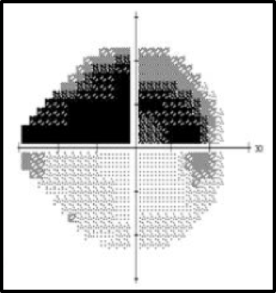

El defecto de campo visual más habitual es un defecto altitudinal superior (Figura 4.) o inferior (el más frecuente).